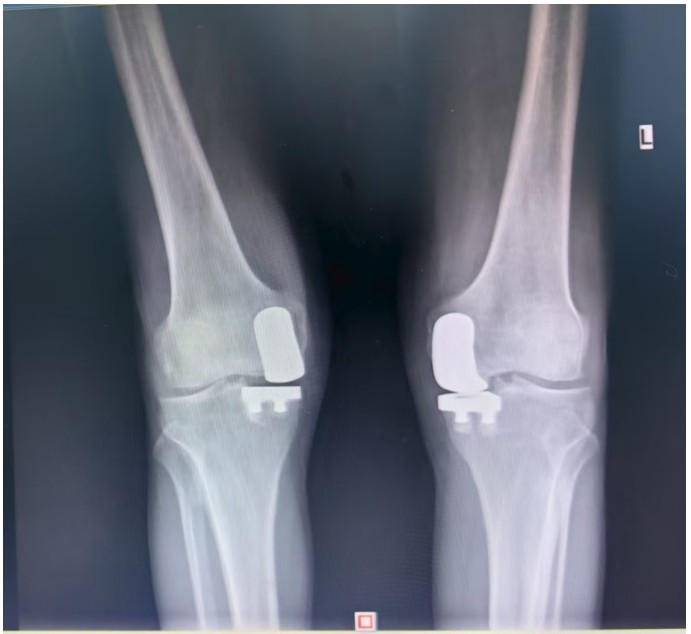

通訊員王珂報(bào)道:近日,一位來(lái)自江西的大爺跨越六百公里,專程來(lái)到衡陽(yáng)市中心醫(yī)院關(guān)節(jié)外科求診。羅湘平主任醫(yī)師、彭健副主任醫(yī)師團(tuán)隊(duì)熱情地接待了患者,成功為其實(shí)施了“雙側(cè)人工膝關(guān)節(jié)單髁置換術(shù)(UKA)”。術(shù)后膝關(guān)節(jié)功能顯著改善,第二天便可下地活動(dòng)雙側(cè)膝關(guān)節(jié)活動(dòng)度輕松達(dá)到90°,對(duì)手術(shù)效果非常滿意9月10日順利出院。

據(jù)了解,患者1年前無(wú)明顯誘因出現(xiàn)雙膝關(guān)節(jié)疼痛,以右側(cè)膝關(guān)節(jié)為主,近5個(gè)月來(lái)雙膝關(guān)節(jié)疼痛明顯加重,不但日常行走困難,生活質(zhì)量更是受到極大影響。經(jīng)多家醫(yī)院治療效果均不理想,了解到衡陽(yáng)市中心醫(yī)院關(guān)節(jié)外科在關(guān)節(jié)置換領(lǐng)域擁有豐富的臨床經(jīng)驗(yàn)和良好的患者口碑,毅然決定赴衡求醫(yī)。醫(yī)生發(fā)現(xiàn)患者雙膝關(guān)節(jié)已內(nèi)翻畸形,關(guān)節(jié)內(nèi)側(cè)骨性膨大,X線提示雙膝退行性病變,雙膝內(nèi)側(cè)間隙明顯狹窄手術(shù)為最佳治療方式。為了達(dá)到根治目的,羅湘平主任醫(yī)師、彭健副主任醫(yī)師為患者進(jìn)行了詳細(xì)查體及綜合評(píng)估,術(shù)前組織開(kāi)展多學(xué)科討論(MDT)。考慮到易叔叔的膝關(guān)節(jié)骨關(guān)節(jié)炎僅局限于內(nèi)側(cè),外側(cè)間室軟骨良好,若采用全膝關(guān)節(jié)置換術(shù)會(huì)將失去正常關(guān)節(jié)間室的軟骨與韌帶,創(chuàng)傷大,便為其制定了右膝關(guān)節(jié)單髁置換手術(shù)治療方案。在充分完善術(shù)前準(zhǔn)備后,羅湘平主任、彭健副主任醫(yī)師團(tuán)隊(duì)為患者實(shí)施了右側(cè)膝關(guān)節(jié)單髁置換術(shù)。手術(shù)過(guò)程順利,團(tuán)隊(duì)?wèi)?yīng)用微創(chuàng)術(shù)式(MIS)及“精準(zhǔn)間隙平衡技術(shù)”,最大程度減少了手術(shù)創(chuàng)傷,為術(shù)后快速康復(fù)奠定了堅(jiān)實(shí)基礎(chǔ),術(shù)后第二天即可借助助行器下地活動(dòng)。6天后團(tuán)隊(duì)順利為患者實(shí)施了左側(cè)膝關(guān)節(jié)單髁置換手術(shù)。目前,易叔叔在關(guān)節(jié)外科醫(yī)護(hù)團(tuán)隊(duì)的精心指導(dǎo)和康復(fù)治療下,恢復(fù)情況良好,雙側(cè)膝關(guān)節(jié)活動(dòng)度輕松達(dá)到90°,膝關(guān)節(jié)功能顯著改善,能夠獨(dú)立下地行走,對(duì)手術(shù)效果非常滿意,9月10日順利出院。